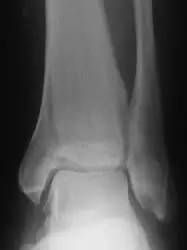

骨挫伤在 X 线和 CT 片上呈阴性,只有 MRI 可以确诊,可见它较隐匿性骨折更为「隐匿」。据研究,MRI 对其诊断的敏感性是 91%~96%,特异性是 86%~96%。我们在骨挫伤的 MRI 片上,常能看到形态各异的骨挫伤图像,如地图状、线状等(图 2)。

图 2 MRI 图像(T1 相)示地图状、线状骨挫伤。(图片摘自 Vellet AD, et al. Radiology,1991,178(1))